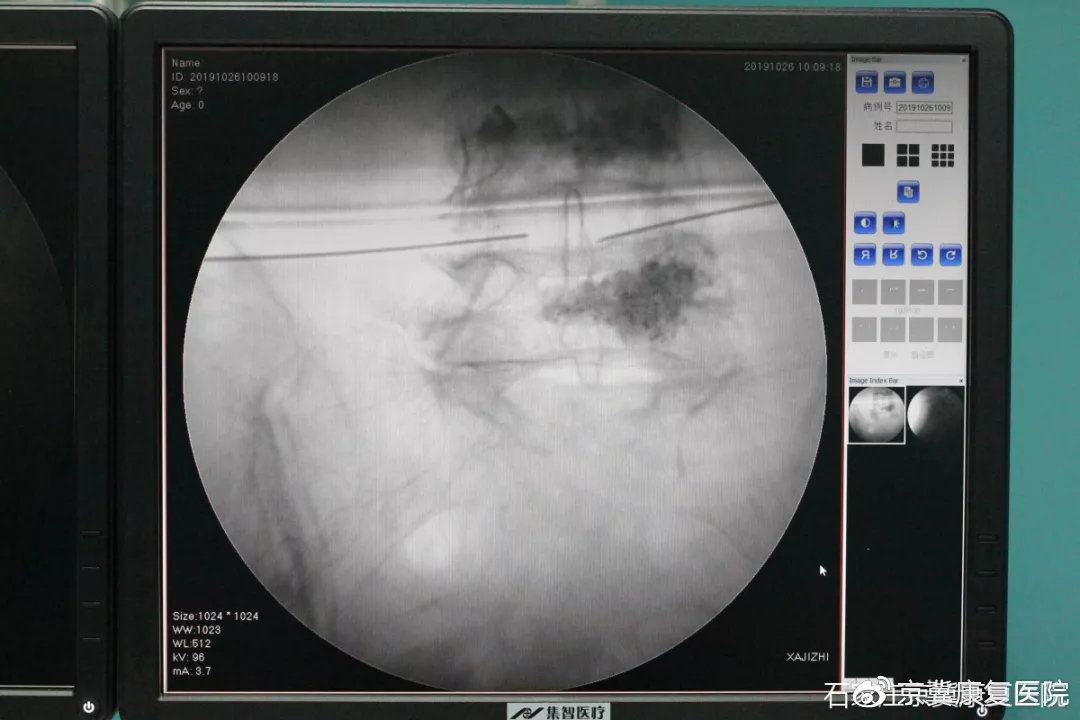

1、安全:治疗过程是在C型臂引导下精确定位,直接作用在病变的椎间盘上,数据精确到1毫米以下,全程操作可视,不会伤及周围正常的组织器官及神经,射频温度可控,确保了治疗前后的安全,不感染,不存在热损伤。

(C型臂引导下靶点定位)